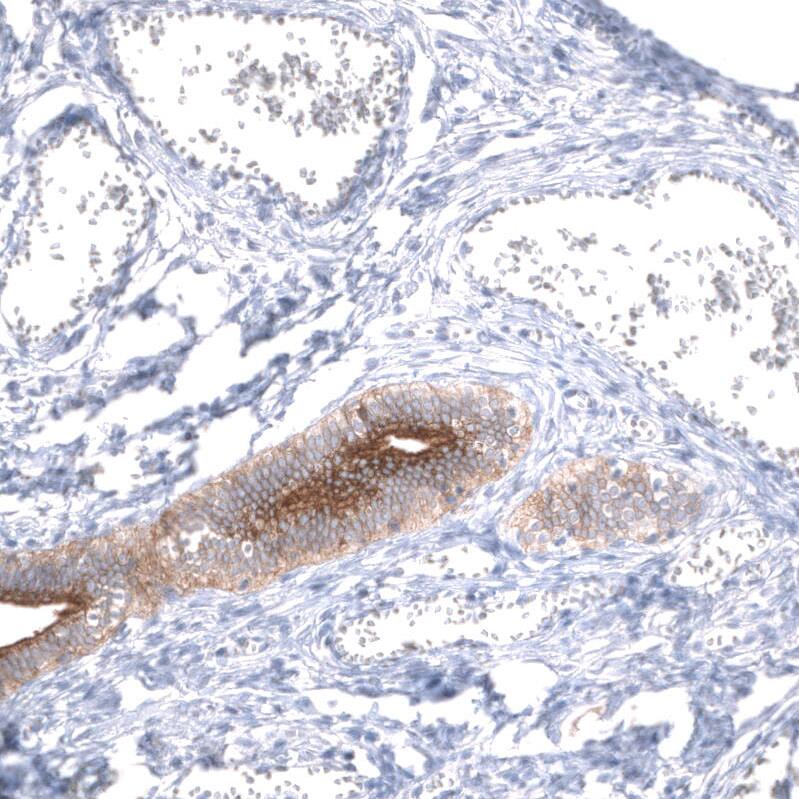

Staining of human fallopian tube shows strong membranous positivity in glandular cells.